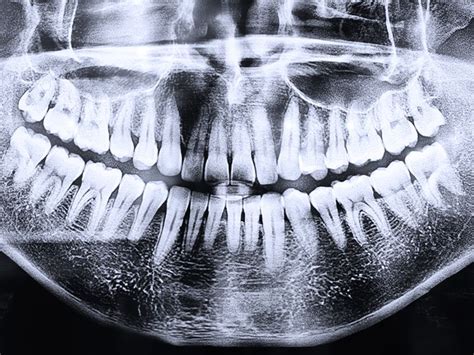

La radiografía panorámica dental, también conocida como ortopantomografía, es una herramienta fundamental en odontología para obtener una visión general de la boca. Permite a los dentistas y ortodoncistas evaluar la salud dental y maxilofacial de manera integral.

Una ortopantomografía es un tipo de radiografía que proporciona una imagen bidimensional de toda la mandíbula, los dientes y las estructuras circundantes en una sola toma. Esta prueba es diferente a otras radiografías ya que se utiliza mucho menos radiación, se realiza en unos pocos segundos y se hace en una sola toma.

- Cobertura Completa: Ofrece una visión completa de ambas mandíbulas (superior e inferior), todos los dientes y las estructuras adyacentes, como los senos maxilares y las articulaciones temporomandibulares.

- Diagnóstico Integral: Permite identificar una amplia gama de problemas dentales, incluyendo caries, enfermedades periodontales, quistes, tumores y anormalidades óseas.

- Evaluación Preoperatoria: Es esencial para la planificación de tratamientos como la colocación de implantes dentales, la extracción de dientes (especialmente las muelas del juicio) y la evaluación ortodóncica.